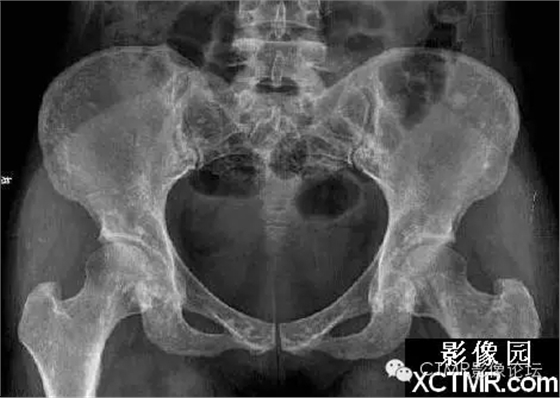

骨斑點(diǎn)癥是一種罕見病,可無任何臨床癥狀。是由于骨內(nèi)具有彌漫性斑點(diǎn)狀致密骨質(zhì)而得名。既往文獻(xiàn)曾稱局限性骨質(zhì)增生癥、彌漫性濃縮性骨病、家族性彌漫性骨硬化癥、點(diǎn)狀致密骨病等。特點(diǎn)為松質(zhì)骨內(nèi)有彌漫性圓點(diǎn)狀致密影。臨床上可無任何癥狀,一般為X線檢查所發(fā)現(xiàn)。可見于任何年齡,男多于女。血鈣、磷正常。

骨斑點(diǎn)癥具有以下特點(diǎn):

(1)本病無臨床癥狀,均為查體或檢查其它病時發(fā)現(xiàn)本病。

(2)本病與年齡性別無關(guān),本組從22~58歲,文獻(xiàn)報(bào)道年齡從4個月~90歲均有發(fā)病。

(3)病灶呈彌漫性多發(fā)的密度增大的圓形、橢圓形、圓圈狀、結(jié)節(jié)狀陰影,其形態(tài)走行,部分與骨的長軸一致。

(4)病灶多累及長骨的兩端,密集于干骺端及骨骺,以及骨盆、手、足及不規(guī)則骨。越靠近關(guān)節(jié)病灶越密集,且密度越濃。病灶可相互融合成片而遮蓋正常骨組織。

(5)密度增濃的斑點(diǎn)狀病灶的邊緣不甚清晰銳利,越靠近中心部位密度越濃,邊緣部位密度略淡。

(6)病灶侵及骨的松質(zhì)骨。骨膜及關(guān)節(jié)軟骨不受侵犯,故關(guān)節(jié)間隙光整清晰。

(7)ECT檢查見顯影后骨骼放射性分布不均勻,骨松質(zhì)內(nèi)有多個大小不等的骨鈣化灶。骨顯像對應(yīng)性放射性增強(qiáng)。據(jù)上述表現(xiàn)視全身骨顯像多處骨代謝增強(qiáng)灶,為骨質(zhì)代謝異常。

(8)本病應(yīng)與成骨性轉(zhuǎn)移相鑒別。成骨性轉(zhuǎn)移首先應(yīng)有原發(fā)性病灶并轉(zhuǎn)移灶呈單發(fā)或散在多發(fā)性骨質(zhì)增濃病灶,無密集對稱性。其病灶直徑均較大,直徑一般在1.0cm以上,同時伴有明顯的疼痛癥狀。與本病鑒別不難。還應(yīng)與蠟淚樣骨相鑒別。